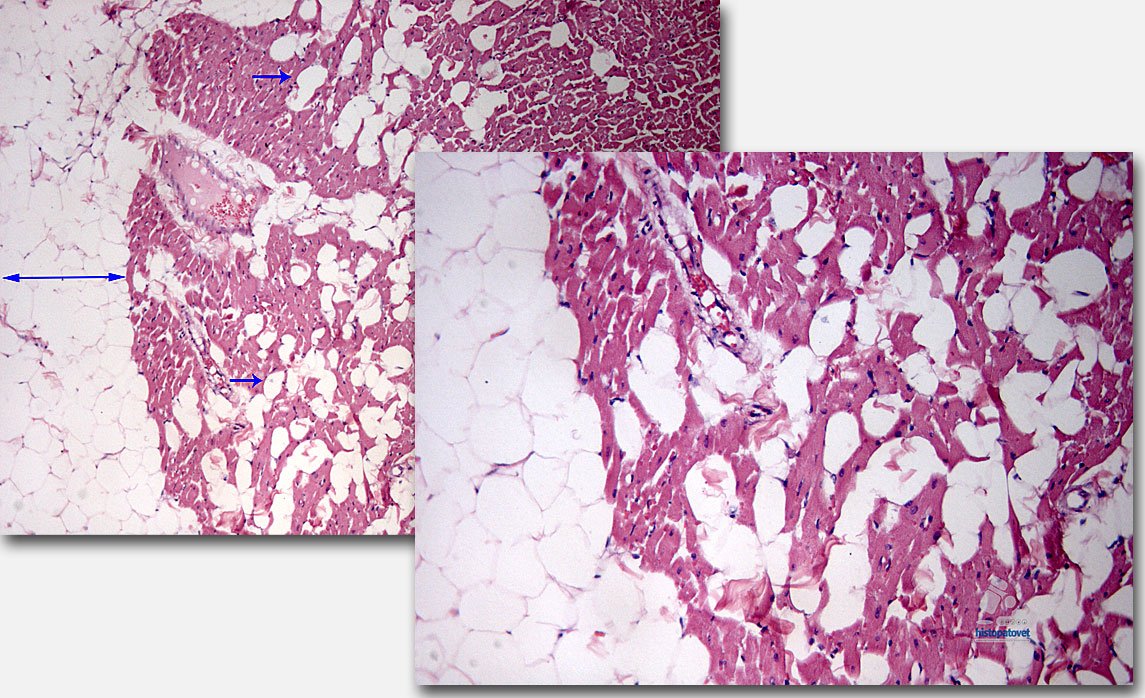

Hallazgos microscópicos: Los principales cambios fueron; la formación de vacuolas vacías en el miocardio especialmente debajo del epicardio. Ver las siguientes cuatro figuras.

Nota: recordar que durante el procesamiento para los tejidos en parafina y luego ser teñidos con Hematoxilina y Eosina se usan alcoholes y xiloles los cuales disuelven la grasa, quedando vacuolas o espacios vacíos.

Fig.3. Miocardio. La flecha grande indica el tejido adiposo subepicárdico, las pequeñas son las vacuolas dentro del miocardio. A la derecha un acercamiento.

Fig.4. A la izquierda el músculo papilar, con vacuolas. A la derecha un vaso sanguíneo con vacuolas, posiblemente de grasa (ver flechas).